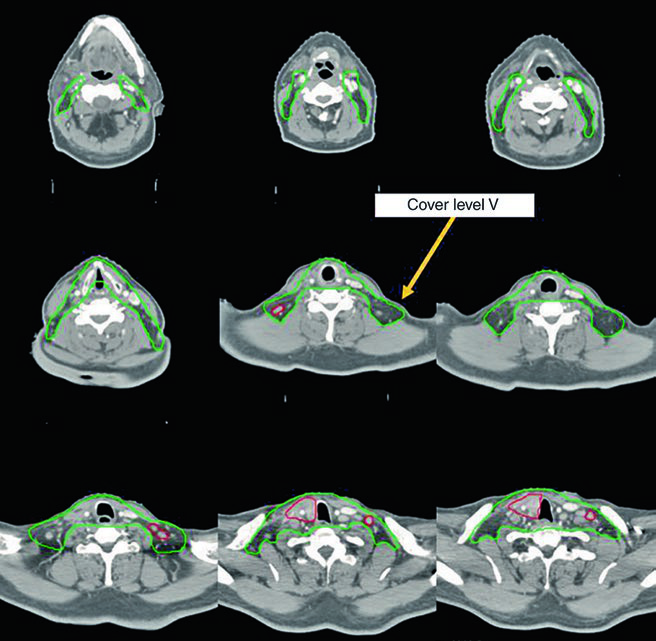

Dois dos cinco casos ilustrativos do livro de referência demonstram o manejo de doença irressecável tratada com quimiorradioterapia definitiva. Ambos receberam plano IMRT com dose-painting simultâneo.

Caso 1 — Carcinoma papilar metastático (Fig. 9.1): Homem de 58 anos com carcinoma papilar metastático de tireoide, submetido a múltiplas ressecções prévias, que se apresentou com recorrência local irressecável e múltiplos linfonodos mediastinais. Recebeu quimiorradioterapia definitiva para prevenir progressão local. O CTV70 Gy (vermelho) abrange a recorrência local e linfonodos mediastinais envolvidos, enquanto o CTV60 Gy (verde) cobre as regiões subclínicas de risco. Este caso exemplifica o cenário de doença recorrente que esgotou as opções cirúrgicas — a radioterapia com dose definitiva é a melhor alternativa para controle local.

Esses dois casos ilustram a versatilidade da IMRT com dose-painting: o plano entrega simultaneamente 70 Gy ao volume de alto risco e 60 Gy ao volume subclínico, sem necessidade de boost sequencial. A escolha de doxorrubicina como quimioterápico concomitante no anaplásico reflete a agressividade dessa histologia e a necessidade de sensibilização ao tratamento, embora as opções sistêmicas tenham evoluído significativamente nos últimos anos.